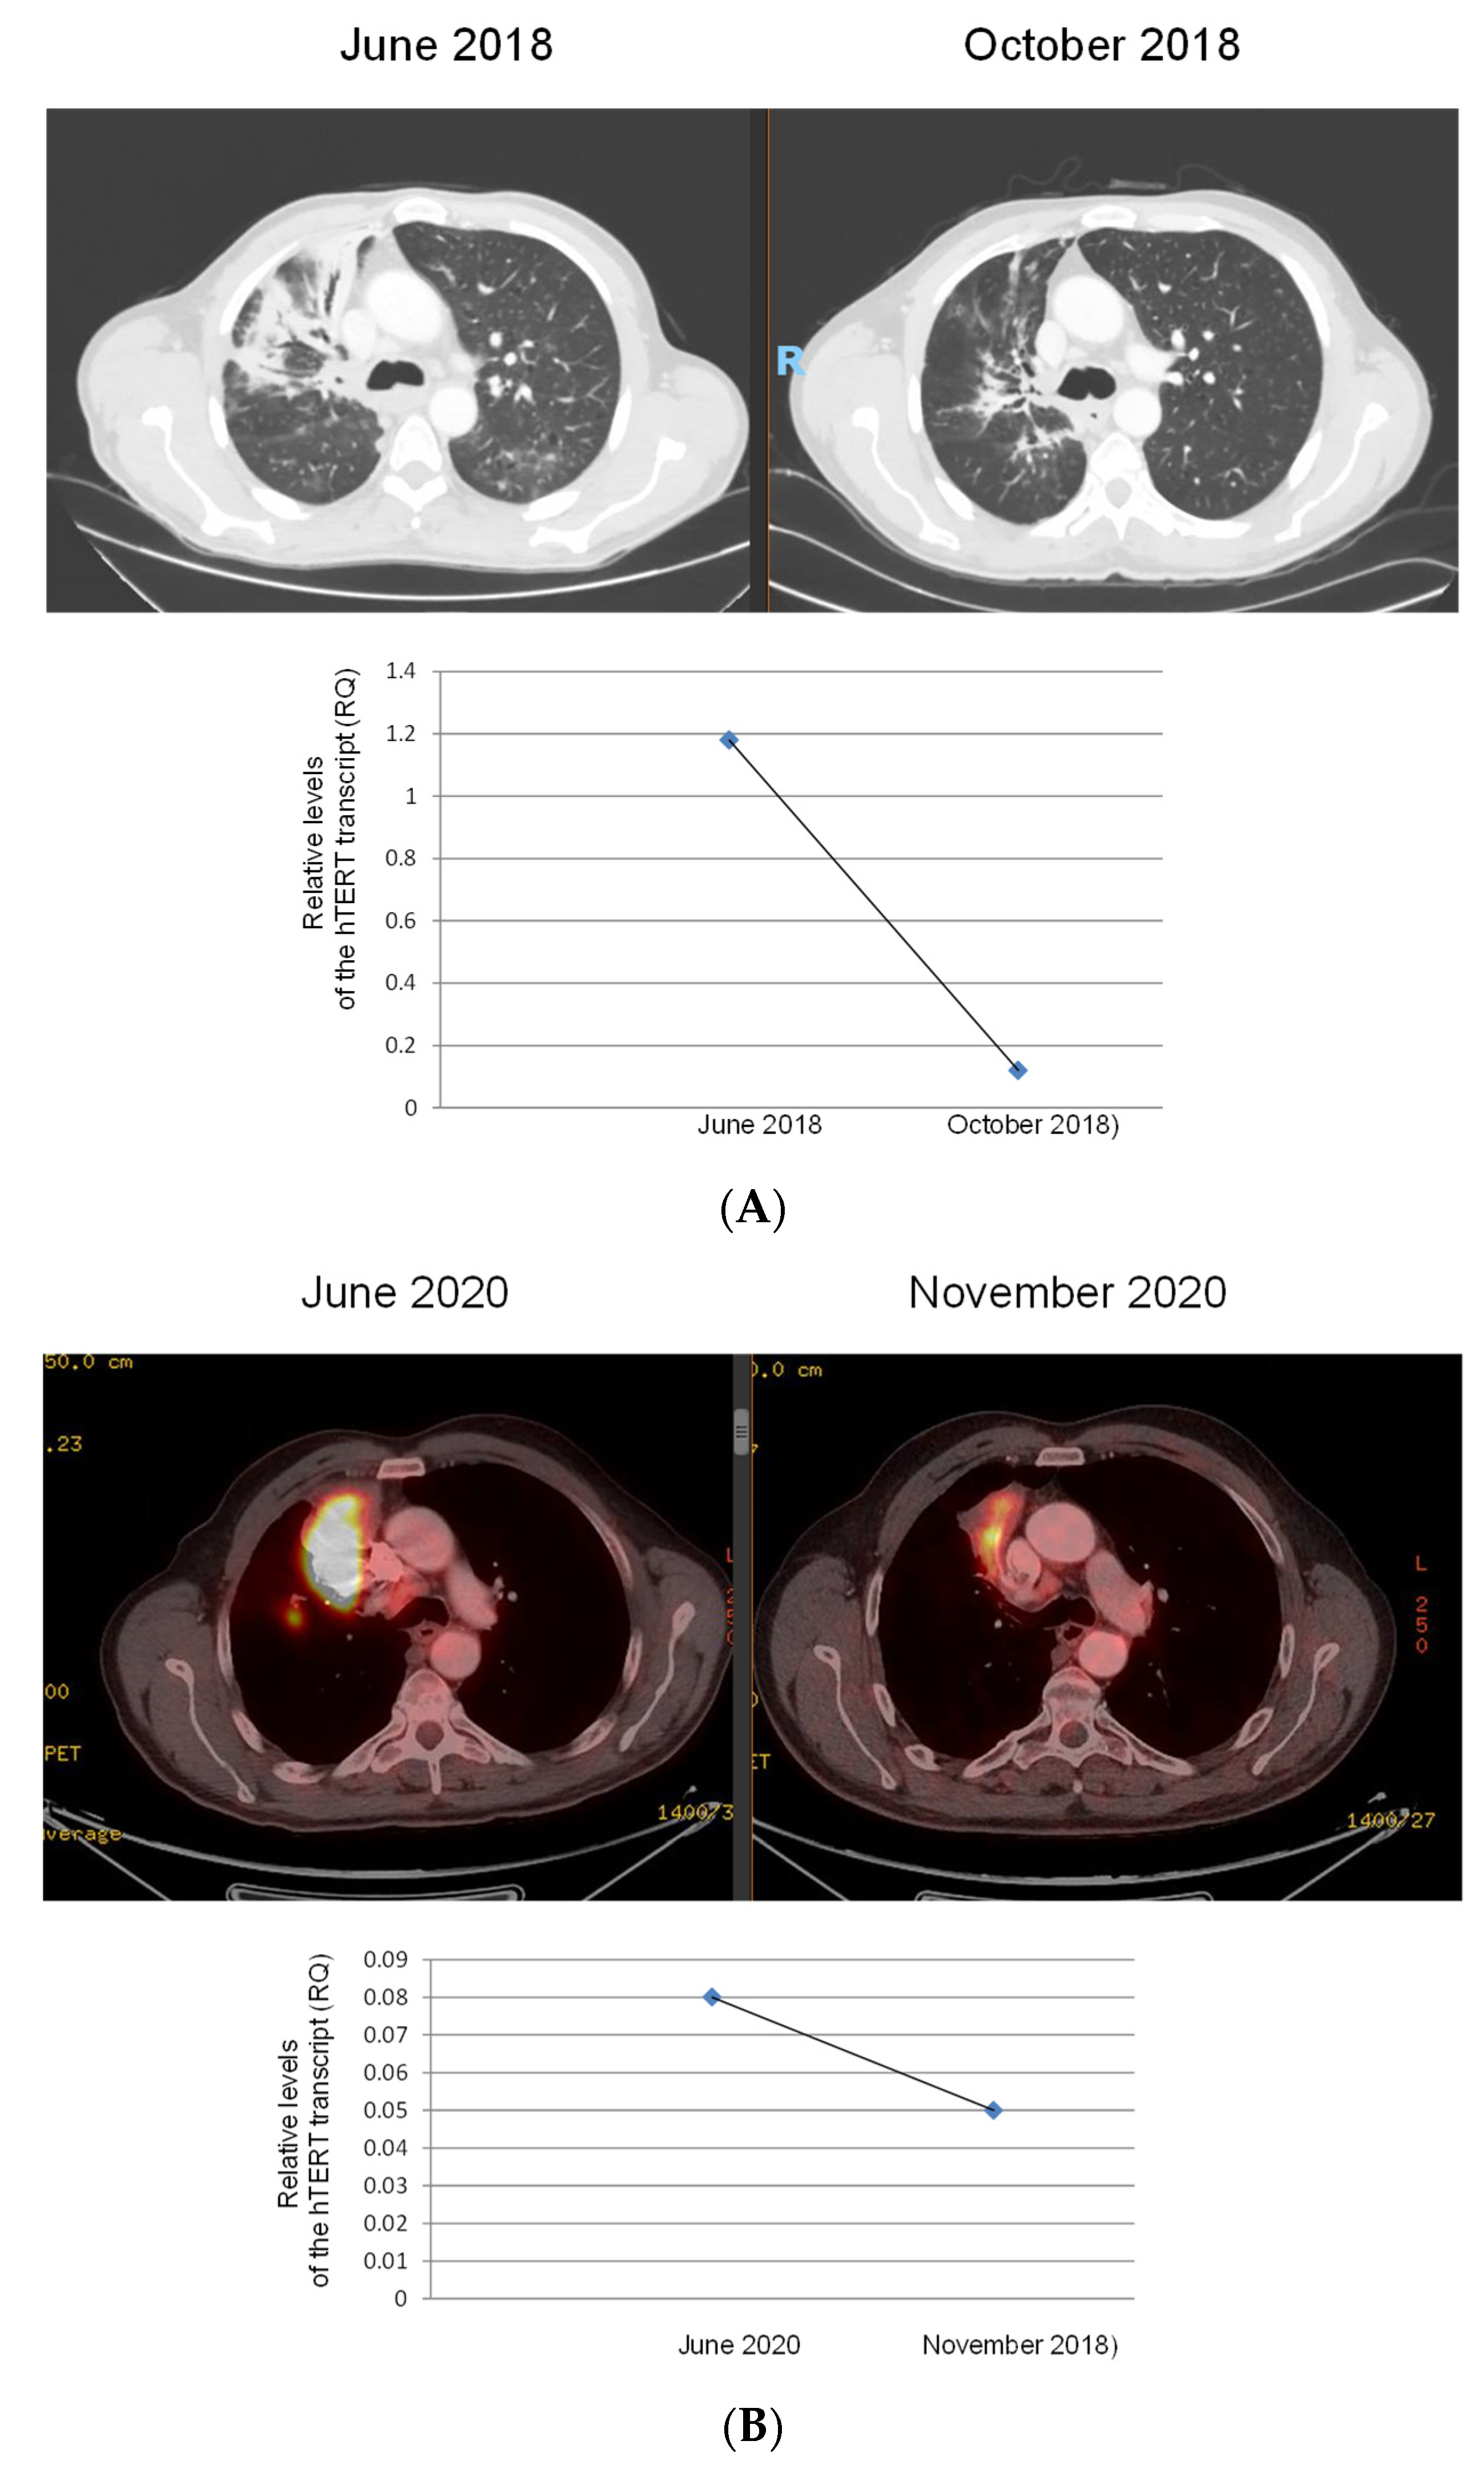

3.4. The Levels of Exosomal hTERT Transcript throughout Follow-Up of the Disease